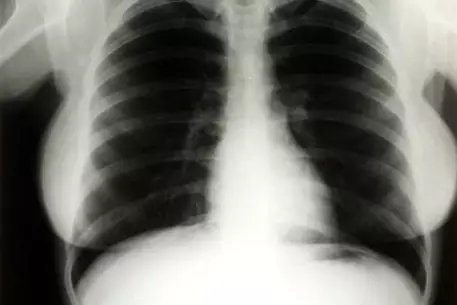

Рентгеновские снимки грудной клетки знаменитой актрисы Мэрилин Монро ушли с молотка за 45 тысяч долларов, сообщает РИА Новости. Лот был представлен на продажу аукционным домом Julien's. Торги прошли с 26 по 27 июня в казино "Планета Голливуд" в Лас-Вегасе. Флюорография была сделана Монро в ноябре 1954 года, когда актриса была госпитализирована в больницу Cedars of Lebanon Hospital во Флориде с диагнозом эндометриоз. Снимки долгое время служили учебным пособием для студентов медицинского университета. Начальная стоимость флюорографии составила более 1200 долларов. Организаторы аукциона планировали выручить за снимки не более трех тысяч долларов. Кто стал обладателем лота, не уточняется. На торгах, помимо рентгеновских снимков, были также представлены и другие вещи, принадлежавшие Монро. Среди них - нераспечатанный флакон духов Chanel №5, кушетка, стоявшая в кабинете личного психотерапевта Монро, деревянные лыжи с инициалами "ММ". Также на аукционе было выставлено кресло, обитое зеленным бархатом. Сидя на нем, актриса позировала во время своей последней фотосессии для журнала Life незадолго до смерти в 1962 году. Напомним, что в середине этого месяца на торгах было куплено розовое платье, в котором Монро снималась в картине "Джентльмены предпочитают блондинок". Именно в нем она исполнила песню "Лучшие друзья девушки - бриллианты". Новый обладатель наряда заплатил за него 312 тысяч долларов.